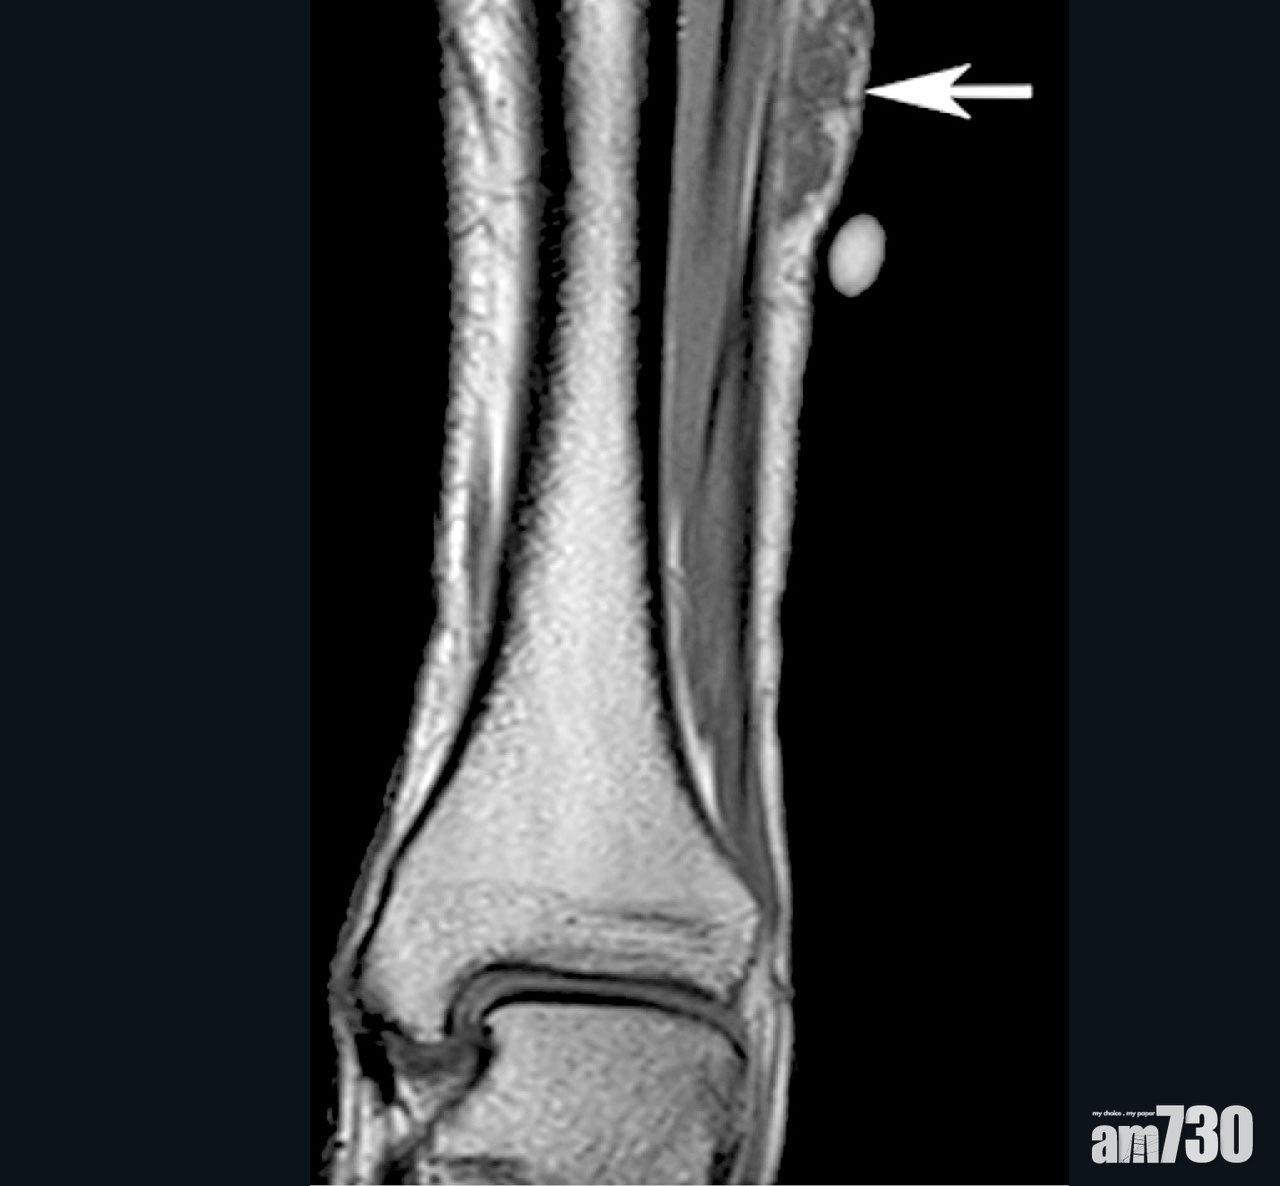

軟組織肉瘤可以侵襲身體不同部位,如四肢及腹部等。

內科腫瘤科專科醫生龍浩鋒指出,軟組織肉瘤的病變來自脂肪、肌肉、纖維、血管和神經線等,佔原發性骨骼肌肉腫瘤大約八成,另外兩成是骨骼肉瘤,「因為此病不常見,坊間甚至醫護人員也認知不多,加上軟組織肉瘤初時很細小或生長在不顯眼位置,又不癢不痛,所以容易與其他疾病混淆,易致延遲治療。」

軟組織肉瘤類型多達70種,而亞洲較常見的是平滑肌肉瘤、惡性纖維組織瘤和滑液肉瘤。如病變位置是四肢或較表面位置,會發現有不明腫塊,未必有痛楚;而腹部的肉瘤則要變大至一定程度,壓著附近的器官才會有疼痛、呼吸不暢等徵狀。龍浩鋒表示,「一旦出現原位復發或者擴散,即屬晚期,常見擴散至肺和肝臟。根據國際研究,患者5年存活率只有一半,晚期患者則只剩15%,而且存活期中位數只得12個月。」